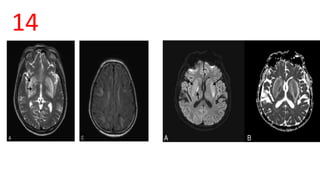

Patient 1 patient 212

Abscess vs GBM

• Capsule is isointense or hyperintense to white matter on T1 and hypointense on T2

• Area of Central Necrosis- Low signal on T1,high signal on FLAIR and T2 (low

density on CT)

• DWI - Restricted

• MRS :Central necrotic area shows alanine, succinate and acetate peaks

Necrotic Tumor vs. Pyogenic Abscess: Differentiation by DWI and ADC

• Necrotic Tumor: Decreased signal intensity on DWI. Increased signal

intensity on ADC maps

• Pyogenic Abscess :Increased signal intensity on DW I Markedly decreased

signal intensity on ADC maps